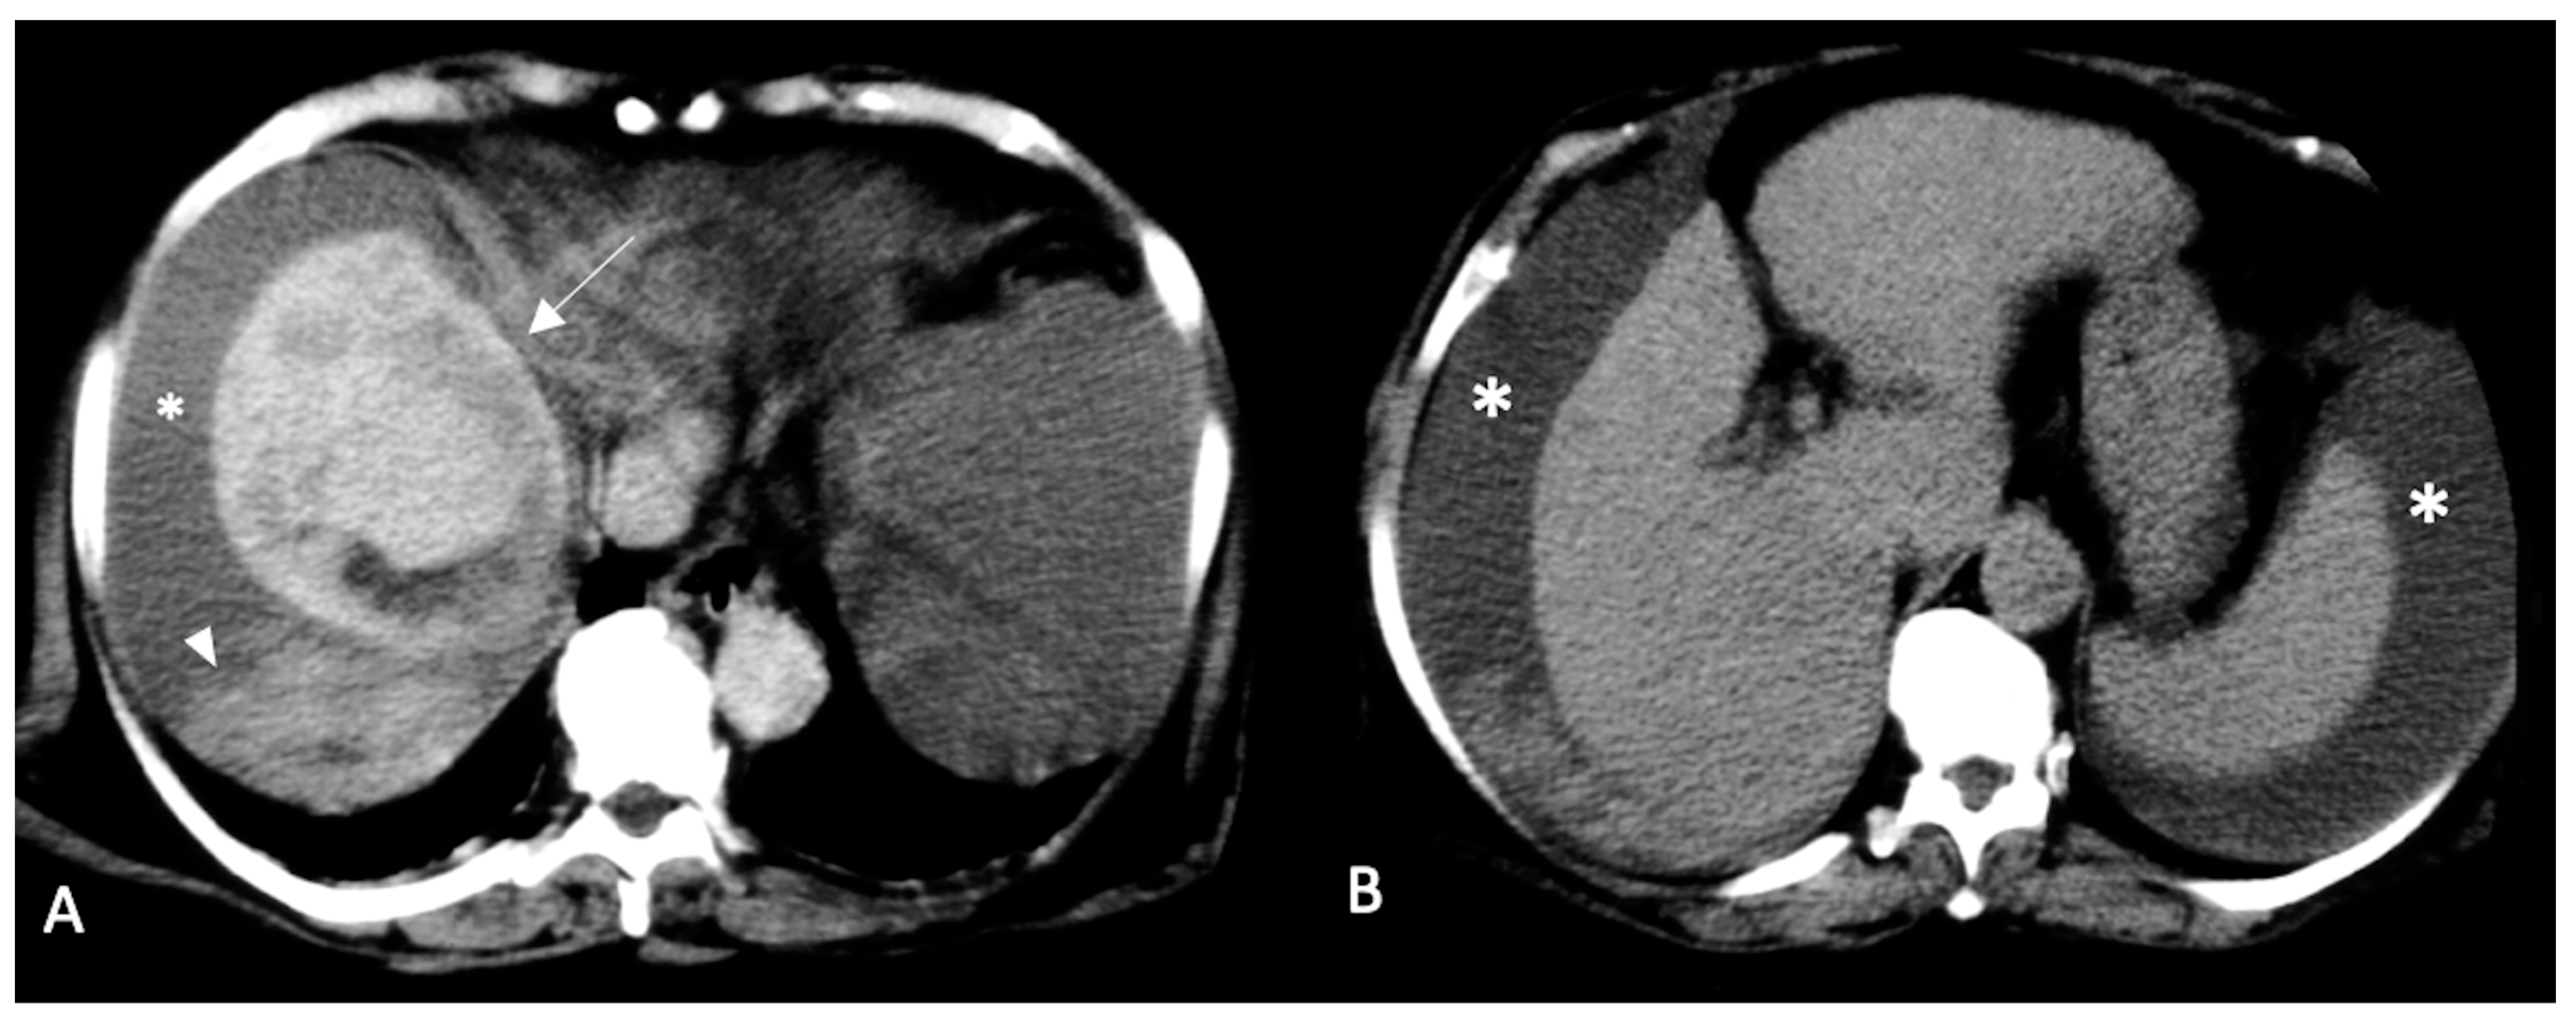

2. CT Findings

2.2. Spontaneously Ruptured HCC (SRHCC)